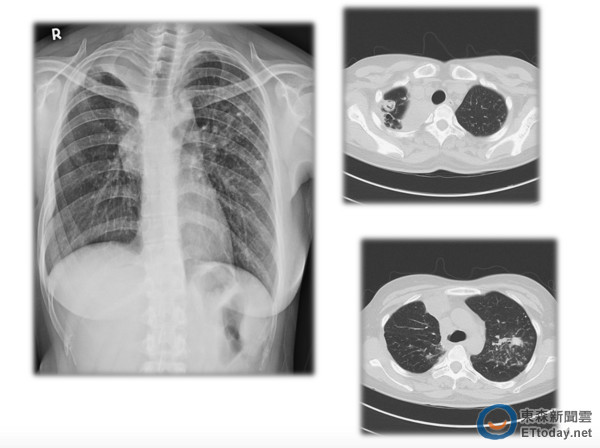

▲肺結核示意圖。(圖/疾管署提供)